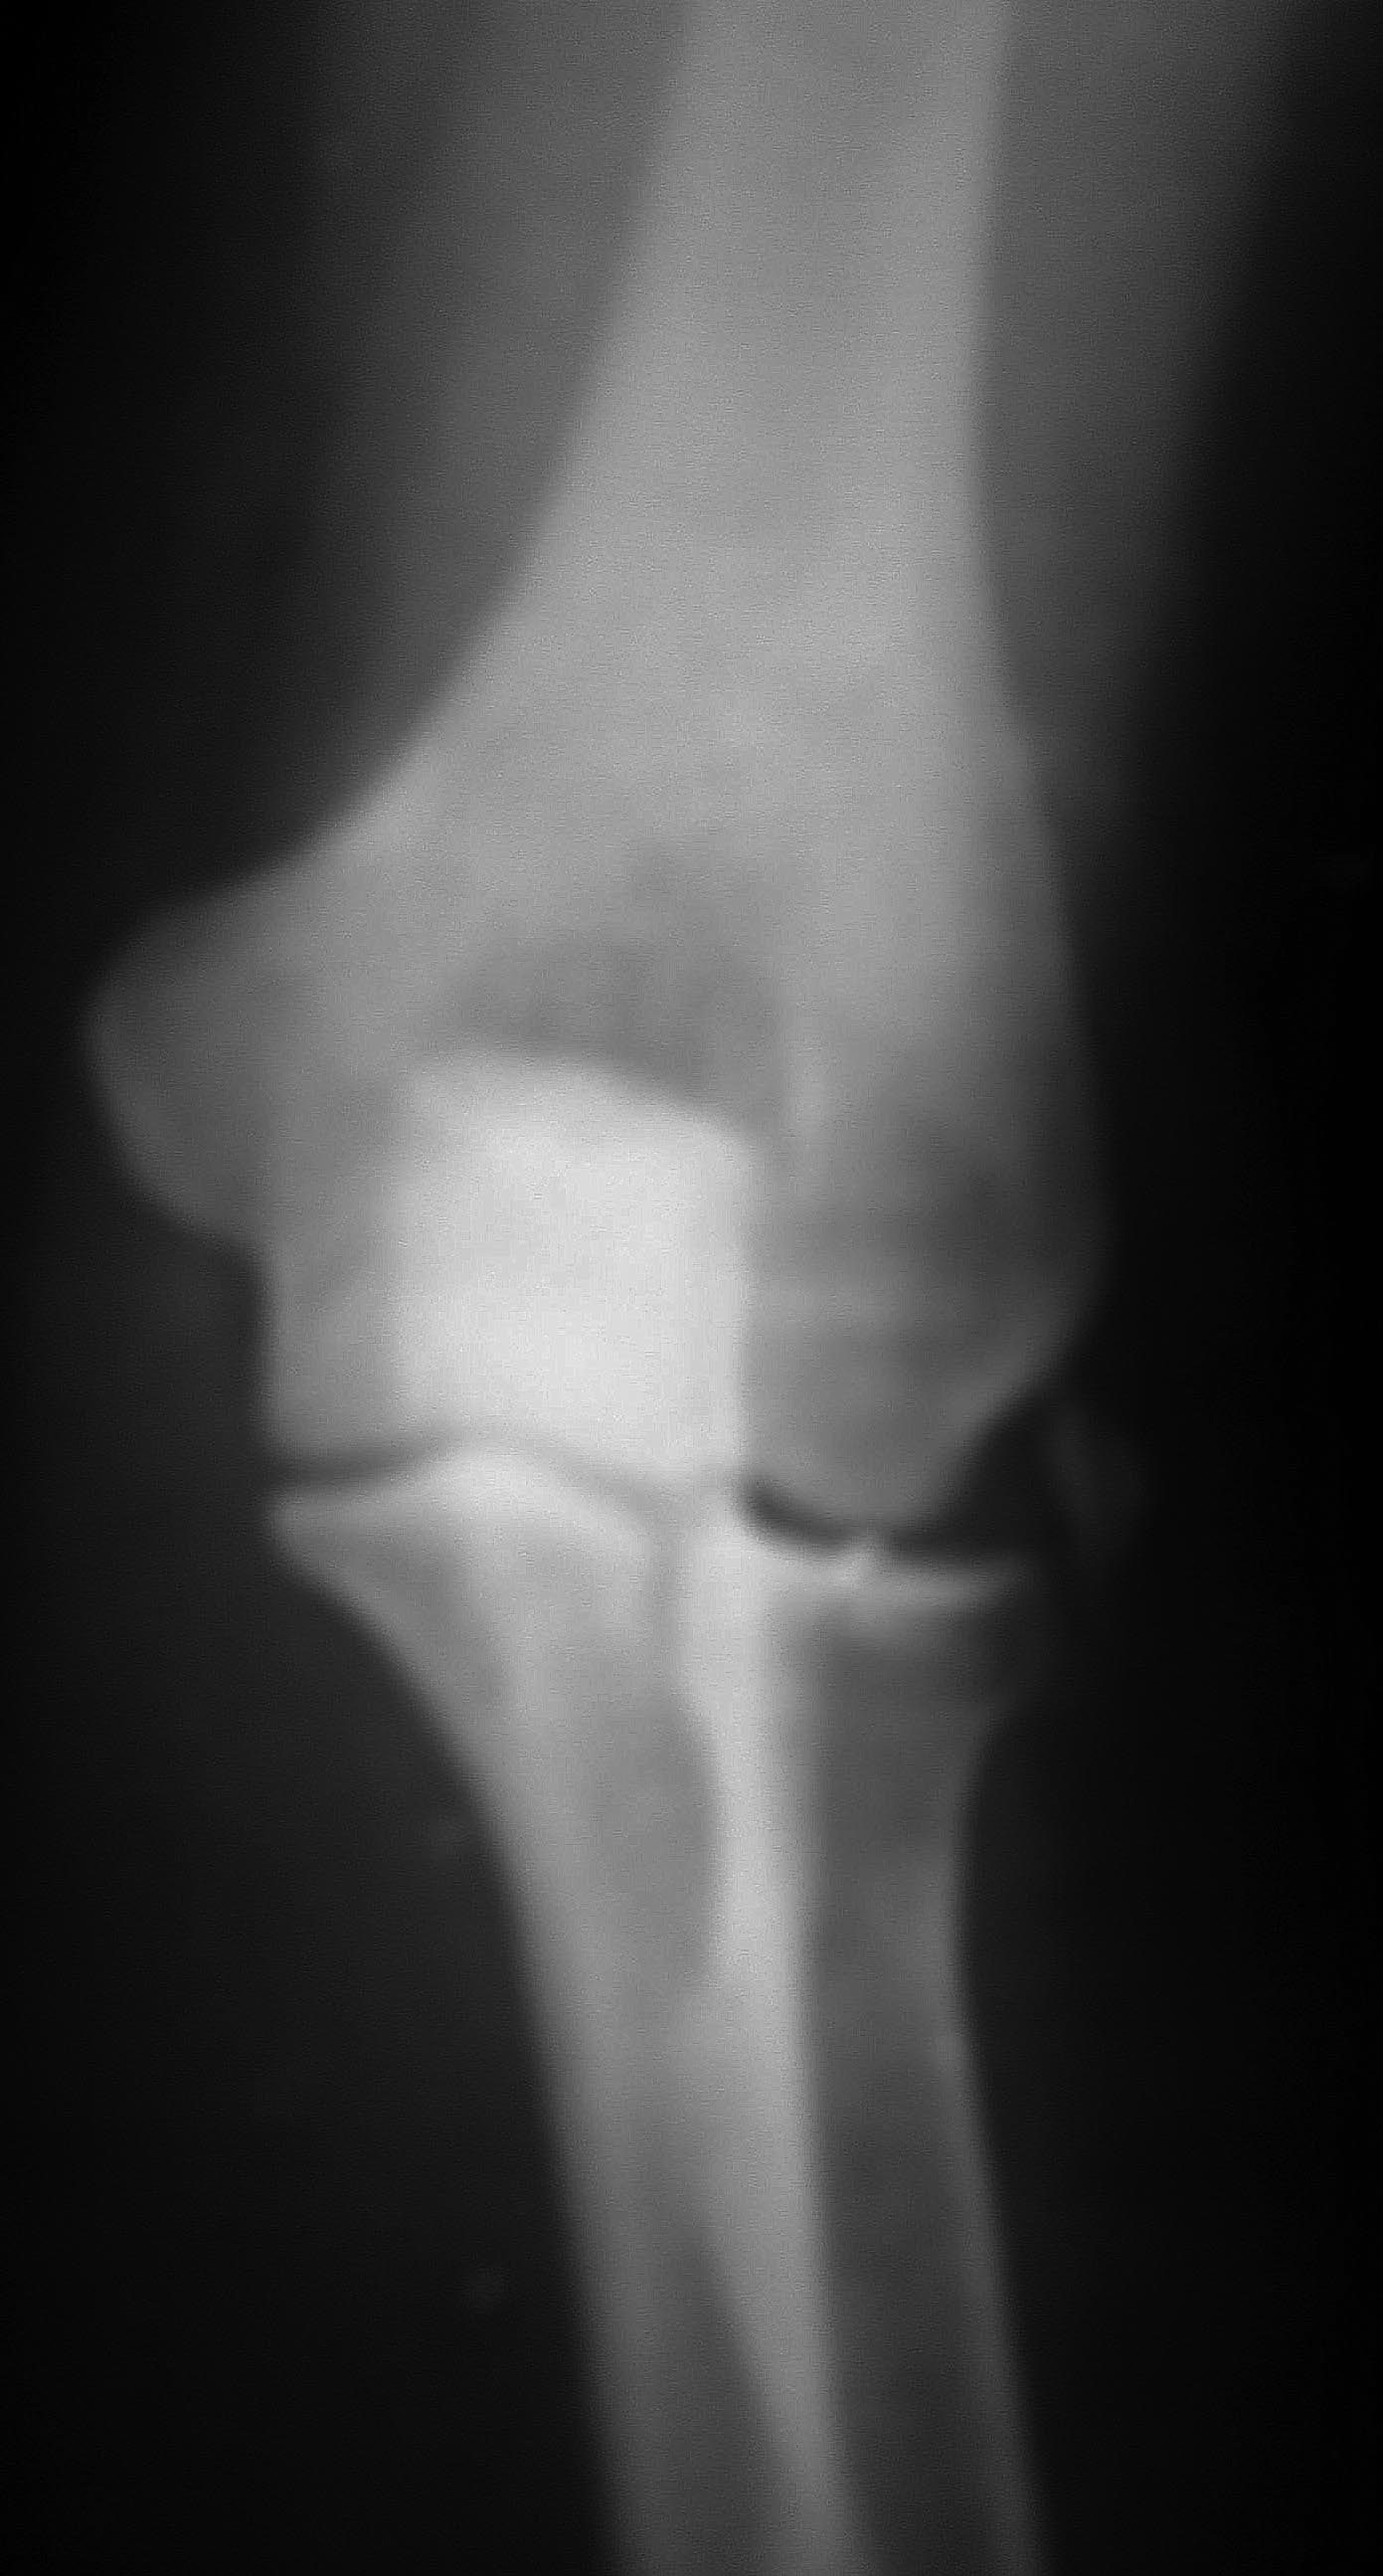

коллеги, помогите опредилиться с диагнозом

На заочную консультацию обратилась девушка, текст переписки и снимки

возможного, боль усилилась, Сделали рентген( в больнице "X")-поставили

диагноз- латеральный эпикондилит. С 17 марта боль стала адской, рука

характерна такая клиника и картинка? Для латерального эпикондилита такая

"отшнуровка" нехарактерна. В каком направлении размышлять, какое

дообследование

назначить?